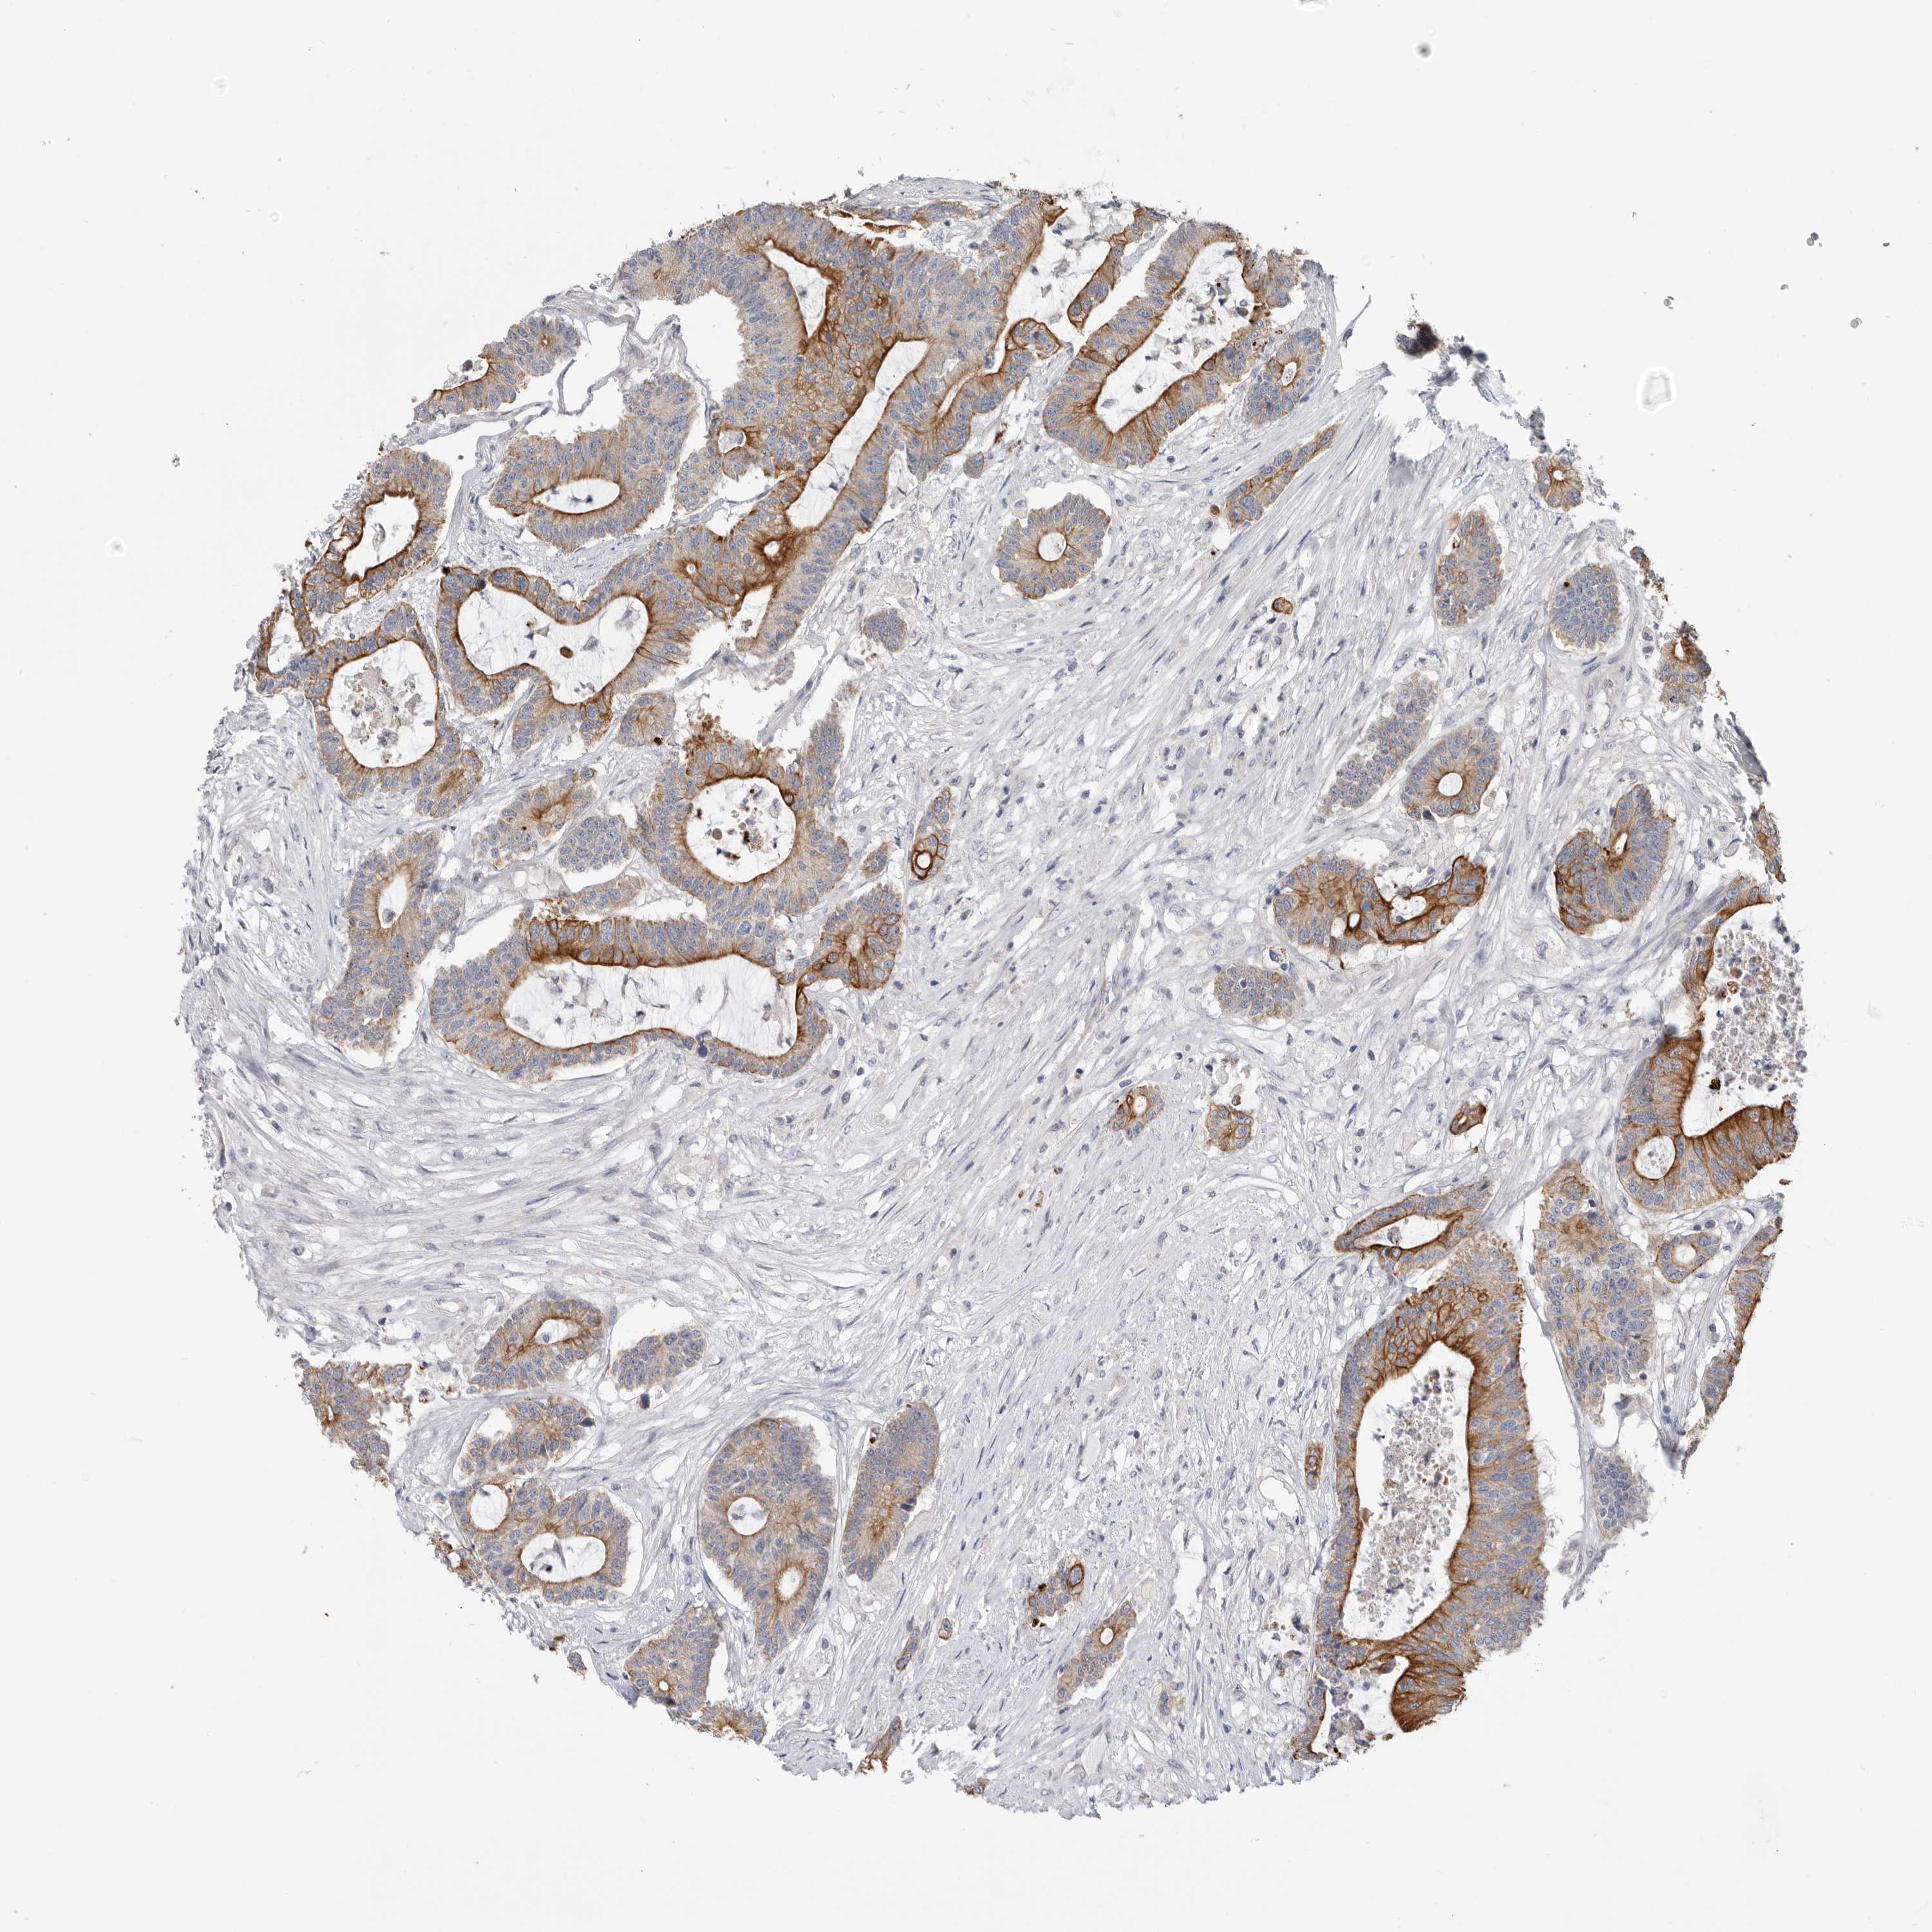

CANCER COLORECTAL CANCER Show tissue menu

Colorectal cancer

Human cancer

Colon adenocarcinoma